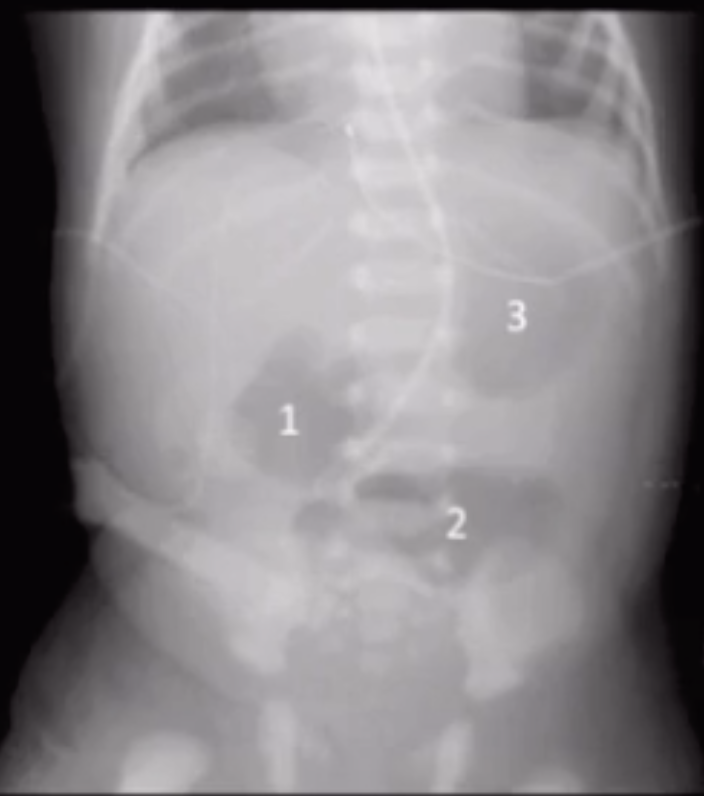

Duodenal obstruction

• Double-bubble

• Dilated stomach in LUQ

• Dilated proximal duodenum in RUQ

• Polyhydraminos

• Cant get food through so eat less, so more fluid

• Need to see an image where the two bubbles connect to ensure it is not another cystic structure

• If do not connect, consider

• Enteric duplication cyst

• Choledochal/ovarian/splenic/liver cyst

• Pseudo-dubble-bubble

• US scan traverses the gastric fundus and antrum-BOTH STOMACH

• Here both bubbles will be in the LUQ

• Get image showing connection and will show just stomach basically